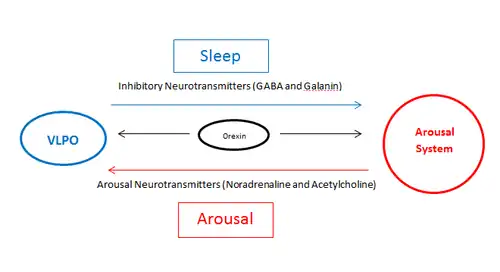

The ventrolateral preoptic nucleus (VLPO), also known as the intermediate nucleus of the preoptic area (IPA), is a small cluster of neurons situated in the anterior hypothalamus, sitting just above and to the side of the optic chiasm in the brain of humans and other animals.[1][2] The brain's sleep-promoting nuclei (e.g., the VLPO, parafacial zone, nucleus accumbens core, and lateral hypothalamic MCH neurons),[3][4][5][6] together with the ascending arousal system which includes components in the brainstem, hypothalamus and basal forebrain, are the interconnected neural systems which control states of arousal, sleep, and transitions between these two states.[1][4][5] The VLPO is active during sleep, particularly during non-rapid eye movement sleep (NREM sleep),[7] and releases inhibitory neurotransmitters, mainly GABA and galanin, which inhibit neurons of the ascending arousal system that are involved in wakefulness and arousal.[1][8] The VLPO is in turn innervated by neurons from several components of the ascending arousal system.[9][10] The VLPO is activated by the endogenous sleep-promoting substances adenosine[11][12] and prostaglandin D2.[13][14] The VLPO is inhibited during wakefulness by the arousal-inducing neurotransmitters norepinephrine and acetylcholine.[9][15] The role of the VLPO in sleep and wakefulness, and its association with sleep disorders – particularly insomnia and narcolepsy – is a growing area of neuroscience research.

The sleep-promoting effects of the VLPO neurons is thought to be due to release of GABA and possibly galanin that suppresses firing of arousal system neurons. As the VLPO is also inhibited by neurotransmitters released by components of the arousal systems, such as acetylcholine and norepinephrine,[9] a current theory has proposed that the VLPO and the arousal system form a "flip-flop" circuit.[1][2] This term from electrical engineering denotes a circuit in which mutual inhibition means that each component of the circuit, as it turns on, turns the other off, resulting in rapid transitions from one state (wake or sleep) to the other, with minimal time in transition states. This theory has been used to create mathematical models that explain much of the wake-sleep behavior in animals, including in pathological states and responses to drugs.[1][24][25] Orexin neurons in the posterior lateral hypothalamus potentiate neurons in the ascending arousal system and help stabilize the brain in the waking state (and consolidated wakefulness, which builds up homeostatic sleep drive, helps stabilize the brain during later sleep). The loss of orexin neurons in the disorder narcolepsy destabilizes the wake-sleep switch, resulting in overwhelming sleep episodes during the waking day, as well as more frequent awakenings from sleep at night.[1]